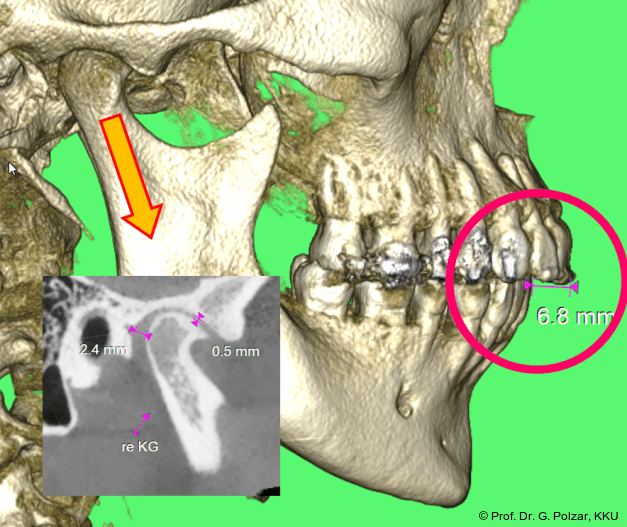

KG-Position: Die 3D-Ansicht im DVT zeigt eine vorverlagerte UK-Position bei neutraler Okklusion (Abb. 4a+b).

Im Sagittalschnitt zeigen beide Kiefergelenke eine deutlich anteriore Position. Der dorsokraniale Abstand betrug rechts 7,0 mm und links 5,8 mm. In der PEP waren sie im lateralen Bereich ca. 1 mm kleiner als in der Mitte der Sagittalprojektion (Abb. 6a–d).

Diese deutlich anteriore Gelenkposition im Neutralbiss ließ den Verdacht auf einen Sunday Bite zu. Das heißt, die Patientin schob den Unterkiefer aktiv nach vorne, um damit schönere Schneidezahnkontakte bzw. eine vermeintlich neutrale Okklusion zu erreichen. Nach mühsamen Lockerungsübungen gelang es der Patientin, auch in die zen­trale Kiefergelenkposition zu wechseln. So zeigte sich das ganze Ausmaß der Malokklusion. In neutraler KG-Position hatte die Patientin eine sagittale Frontzahnstufe von ca. 7 mm mit 1 PB Klasse II-Okklusion im Seitenzahn­bereich (Abb.5a+b, 7a–c).